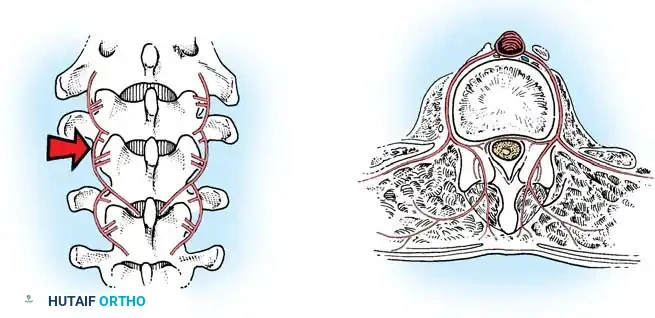

Lateral Exposure and Hemostasis

- Transverse Process Exposure: Extend the subperiosteal dissection laterally, first exposing the facet joints, and then continuing out to the tips of the transverse processes bilaterally.

- Segmental Vessels: As you dissect lateral to the facet joints, you will encounter the posterior branches of the segmental vessels. These must be meticulously identified and coagulated with bipolar or monopolar cautery to prevent insidious bleeding.

Fig. 38-24: Posterior view of segmental vessels located just lateral to each facet joint, requiring meticulous coagulation.

- Facet Cleaning: Use a sharp curet and a pituitary rongeur to completely excise the facet capsules and clean the interspinous ligaments.

Clinical Pearl: Always direct your curet from the midline laterally when cleaning the facet joints. This directional force ensures that if the instrument slips, it moves safely away from the spinal canal, preventing catastrophic dural tears or iatrogenic spinal cord injury.